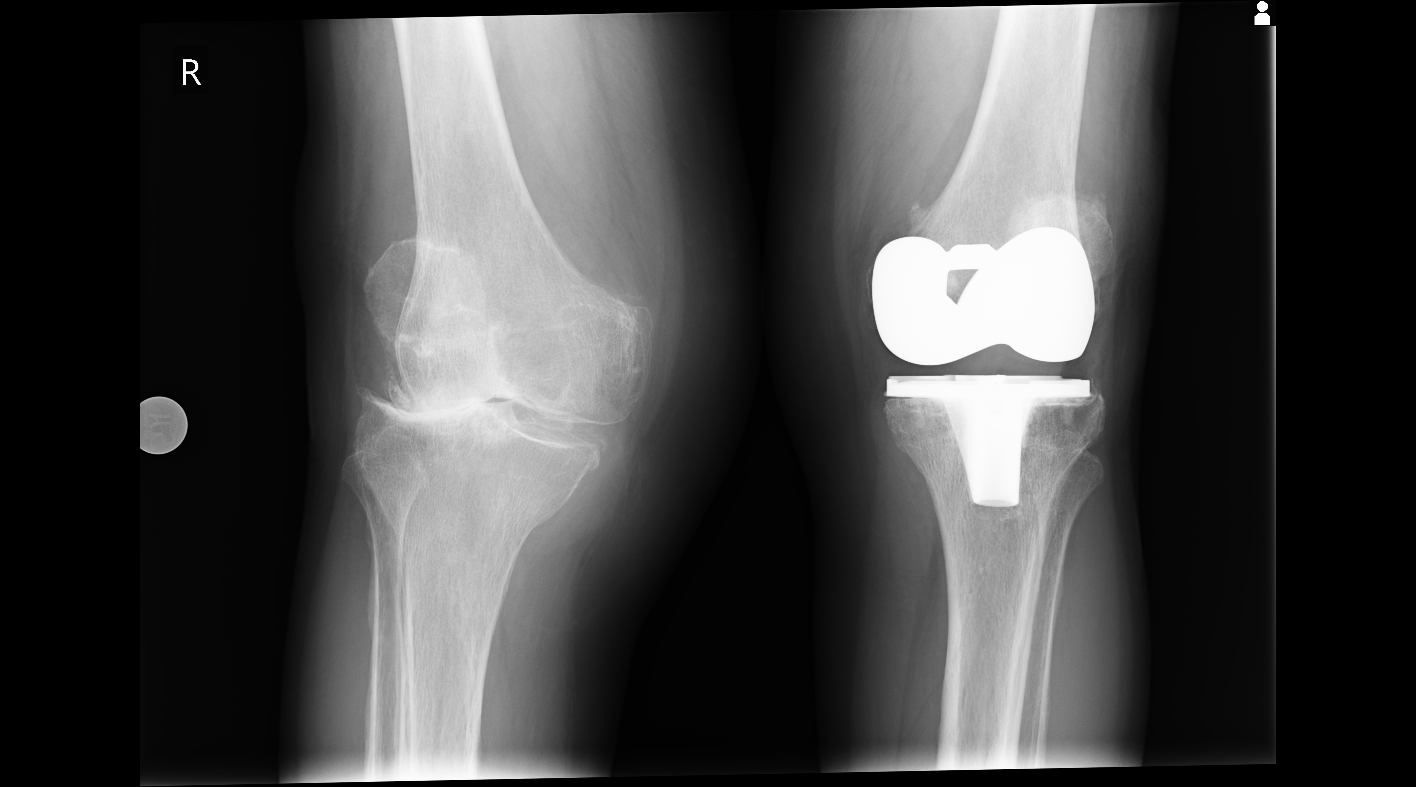

Artroza (osteoartritis) je degenerativna bolest zglobova kod koje hrskavica zgloba postupno propada. Hrskavica je glatko, elastično tkivo koje oblaže krajeve kostiju i omogućuje im kretanje bez trenja. Kada se stanje ili ošteti, kosti počinju trljati jedna o drugu, što dovodi do boli, ukočenosti i smanjene funkcije zglobova.

Kada konzervativne metode više ne daju rezultate i kvaliteta života je ozbiljno narušena, razmatra se operacija - od manjih korektivnih zahvata do ugradnje umjetnog zgloba.